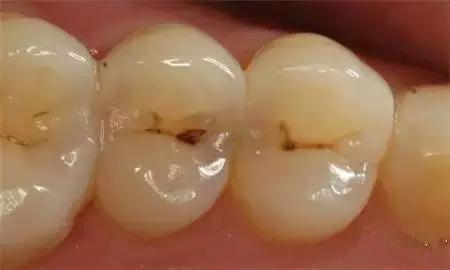

step1:浅龋

当我们身上有小黑点出现时,你对我们漠不关心,说:“没事,不用管。”

牙医说:“龋病主要是由细菌引起的,细菌在牙齿表面形成菌斑,在唾液、牙、细菌、饮食的共同影响下,牙齿硬组织逐渐被破坏。刚开始浅龋只附在牙釉质层,需要做药物治疗或充填治疗。